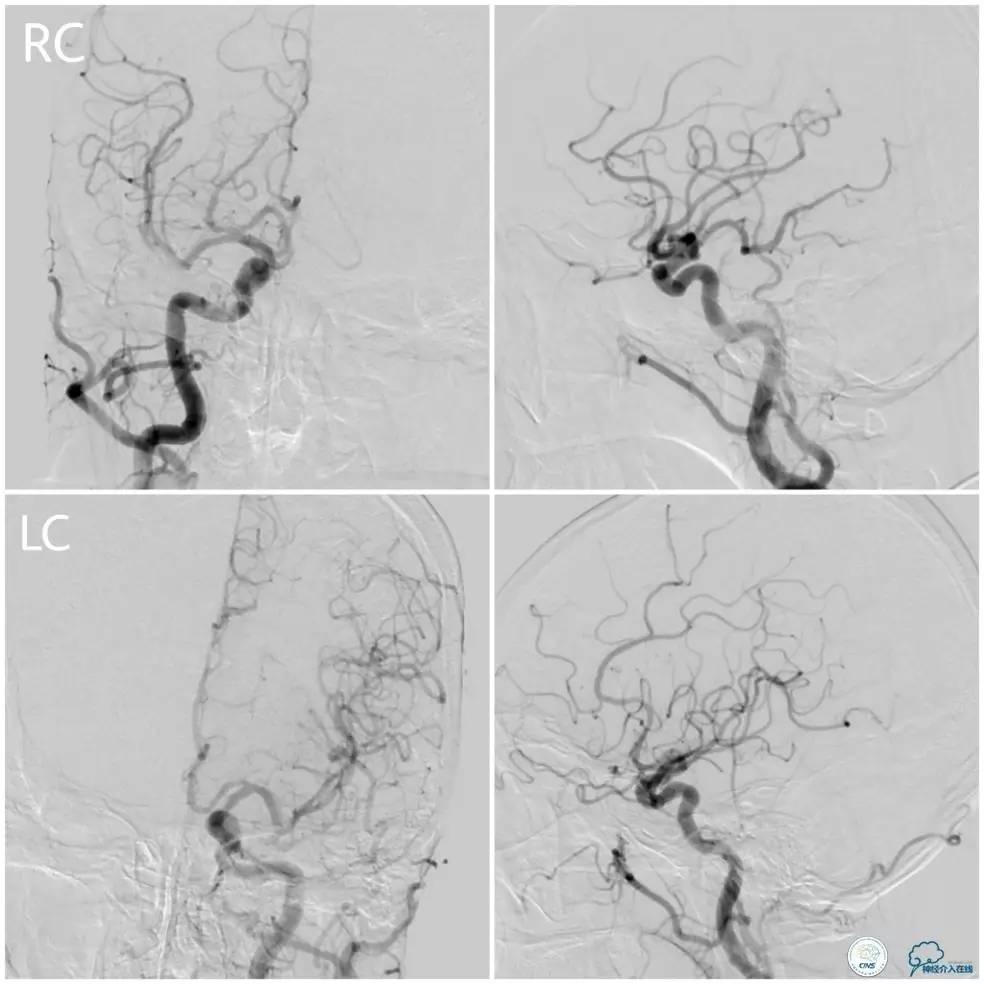

术前DSA:左椎动脉优势,V1及V2段迂曲,V4段狭窄(图5),右椎动脉V2段迂曲(图6)。见右前循环通过后交通动脉向后循环部分区域代偿(图7)。

图5

图6

图7